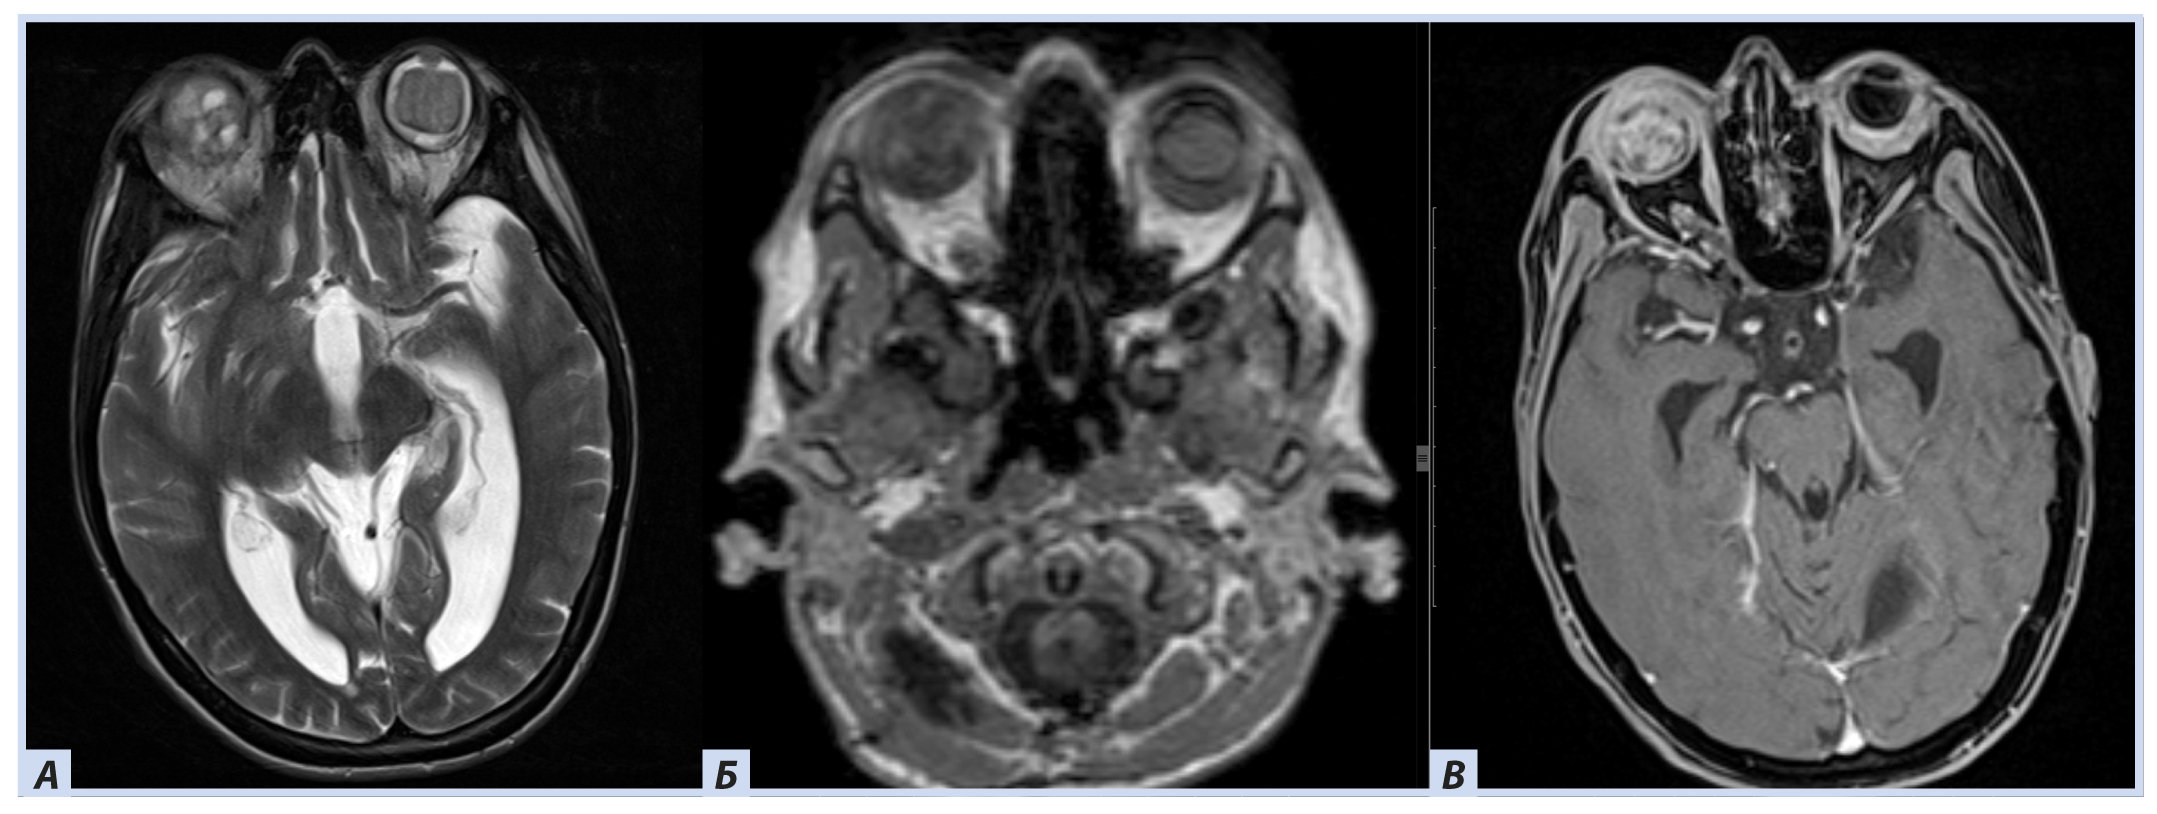

Лучевые методы. На МРТ-изображениях головного мозга выявлено характерное двустороннее поражение глаз (рис. 1), по данным КТ — с участками обызвествления (рис. 2). Также на КТ головного мозга были выявлены зона послеоперационных кистозно-глиозных изменений с наличием кисты и узла на уровне посттрепанационного дефекта в правом полушарии мозжечка, а также аналогичные зоны дорзальнее и в субкортикальных отделах; в левой гемисфере мозжечка определялись кистозные изменения (рис. 3).

Рис. 3. Пациентка П., 30 лет, с диагнозом «Болезнь Гиппеля−Линдау»: магнитно-резонансная томография головного мозга

Примечание. А — Tirm-режим: на фоне кист мозжечка визуализируется мягкотканный компонент, прилегающий к кисте справа; Б — DWI-режим: зона рестрикции диффузии по ходу стенки кисты справа; В — постконтрастное Т1-взвешенное изображение, режим подавления сигнала от жира: в той же зоне отмечается накопление.

В спинном мозге больной на уровне шейного отдела были выявлены кистозные полости с узлами гемангиобластом (рис. 4).

Рис. 4. Пациентка П., 30 лет, с диагнозом «Болезнь Гиппеля−Линдау»: магнитно-резонансная томография спинного мозга

Примечание. А — постконтрастное Т1-взвешенное изображение, режим подавления сигнала от жира: отмечается узел (гемангиобластомы) с аккумуляцией гадолинийсодержащего контраста; Б — Tirm-режим: на фоне кист спинного мозга визуализируется мягкотканный компонент, краниально прилегающий к кисте.